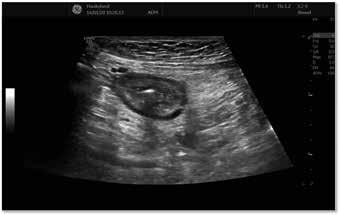

UL av tarm er vanskeligere ved frisk tarm men patologi som her "lyser opp" som en "target lesion" når Crohn pasienter har forverring med fortykket vegg i tynntarm.

2. Ultralyd av tarm (GIUS). IBD-leger over hele verden har nå fått øynene opp for nytteverdien av å kunne visualisere tynn- og tykktarm «bedside» med ultralyd og dermed kunne ta raske beslutninger om behandling. Alternativet er ofte å vente på en invasiv koloskopi, eller MR tynntarm, hvor svaret ofte kommer flere uker etter henvisning.